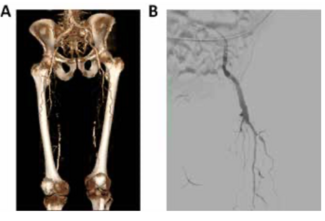

Retrograde pedal access may allow the treatment of superficial femoral artery occlusive lesions when standard endovascular techniques fail. Here, we aimed to analyze the outcomes of this approach in patients with chronic limb ischemia who had...

The authors comment on the article by Papoyan et al, "Retrograde Pedal Access for the Superficial Femoral Artery Recanalization In Critical Limb Ischemia."